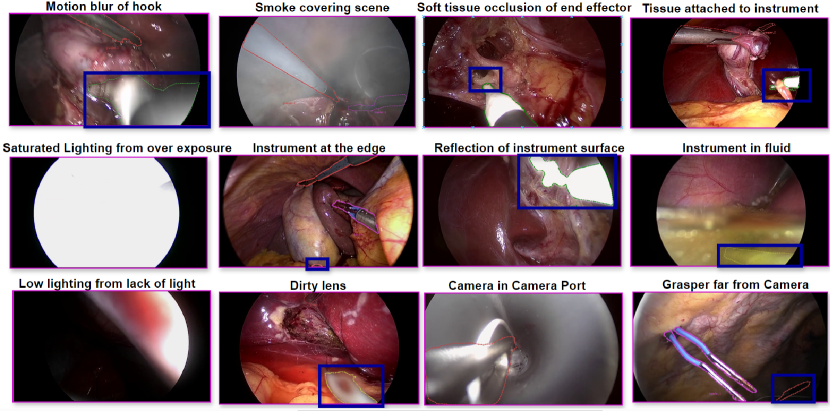

Annotation of Hard Cases: CholecInstanceSeg captures routine surgical procedures, numerous challenging scenarios were encountered. We accounted for twelve specific situations: motion blur, presence of smoke, occlusion by soft transparent tissues or blood, tissues attached to instruments, instruments at the edge of the frame, instruments far from the camera, light reflection, low lighting conditions, bright lighting conditions, lens dirtiness, camera in camera port, and instruments in liquid. Specialized instructions and examples were provided to annotators, including checking neighbouring frames for clarification, utilizing the expected shape of the instrument when in doubt, annotating as much of the instrument as possible, and annotating even under low visibility conditions. A visual representation of these hard cases can be seen in Figure 5. More detailed information about specialized instructions given to annotators for hard cases is added as supplementary material for this manuscript.